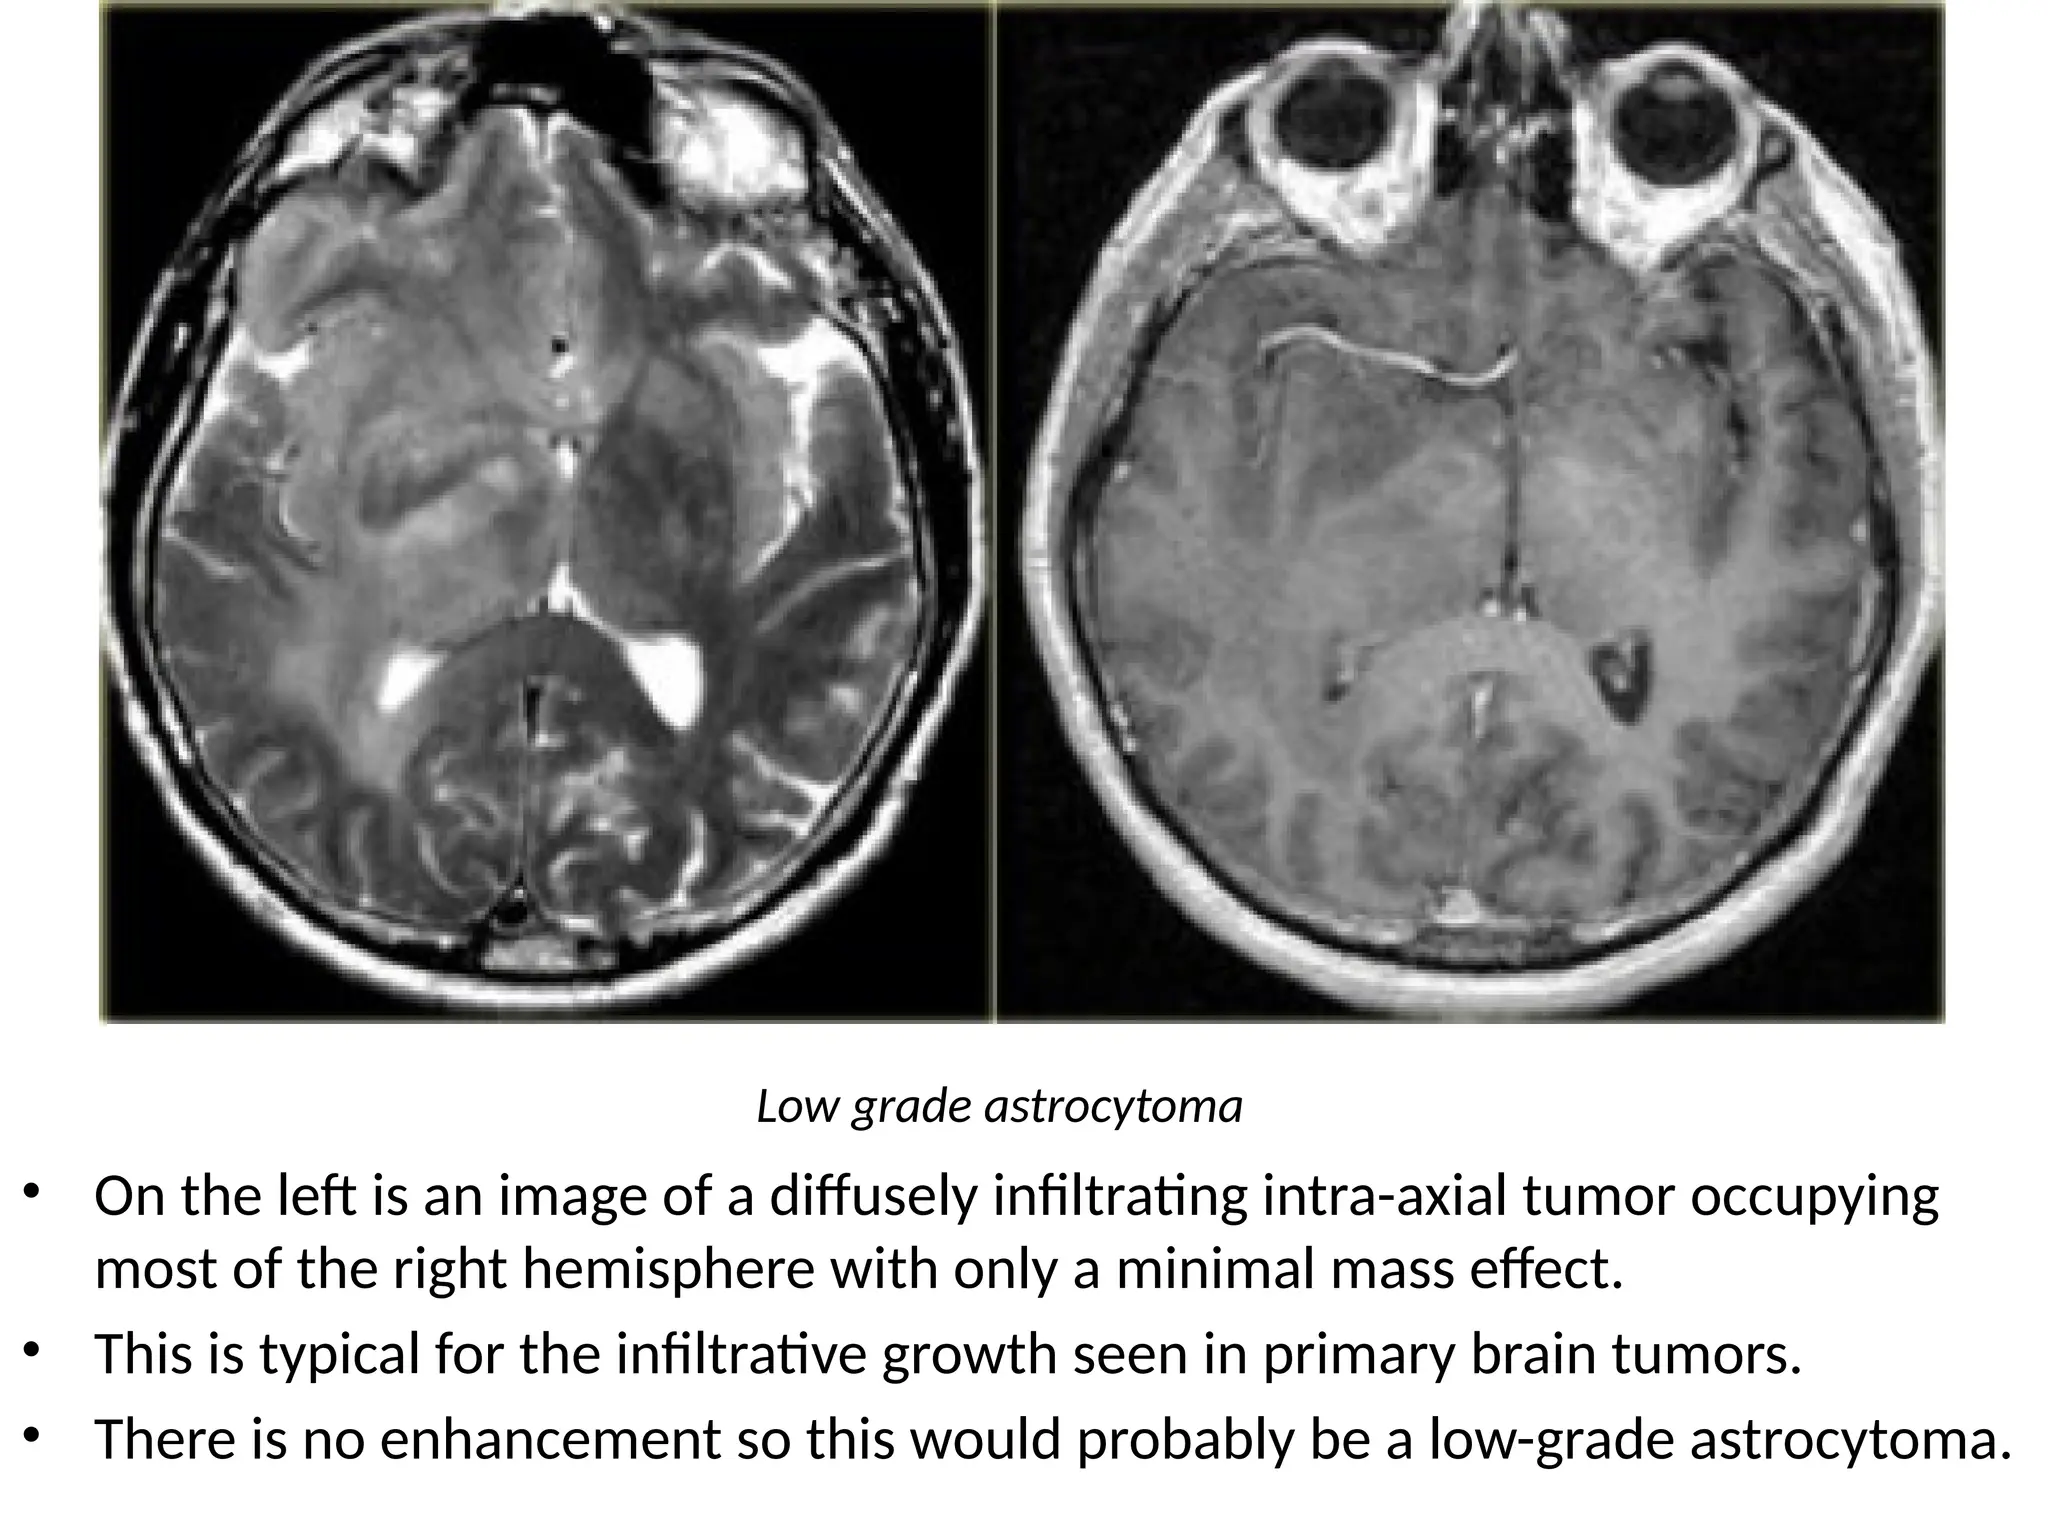

• On the left is an image of a diffusely infiltrating intra-axial tumor occupying

most of the right hemisphere with only a minimal mass effect.

• This is typical for the infiltrative growth seen in primary brain tumors.

• There is no enhancement so this would probably be a low-grade astrocytoma.

Low grade astrocytoma